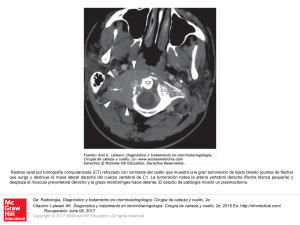

Slide 1 - Access Medicina